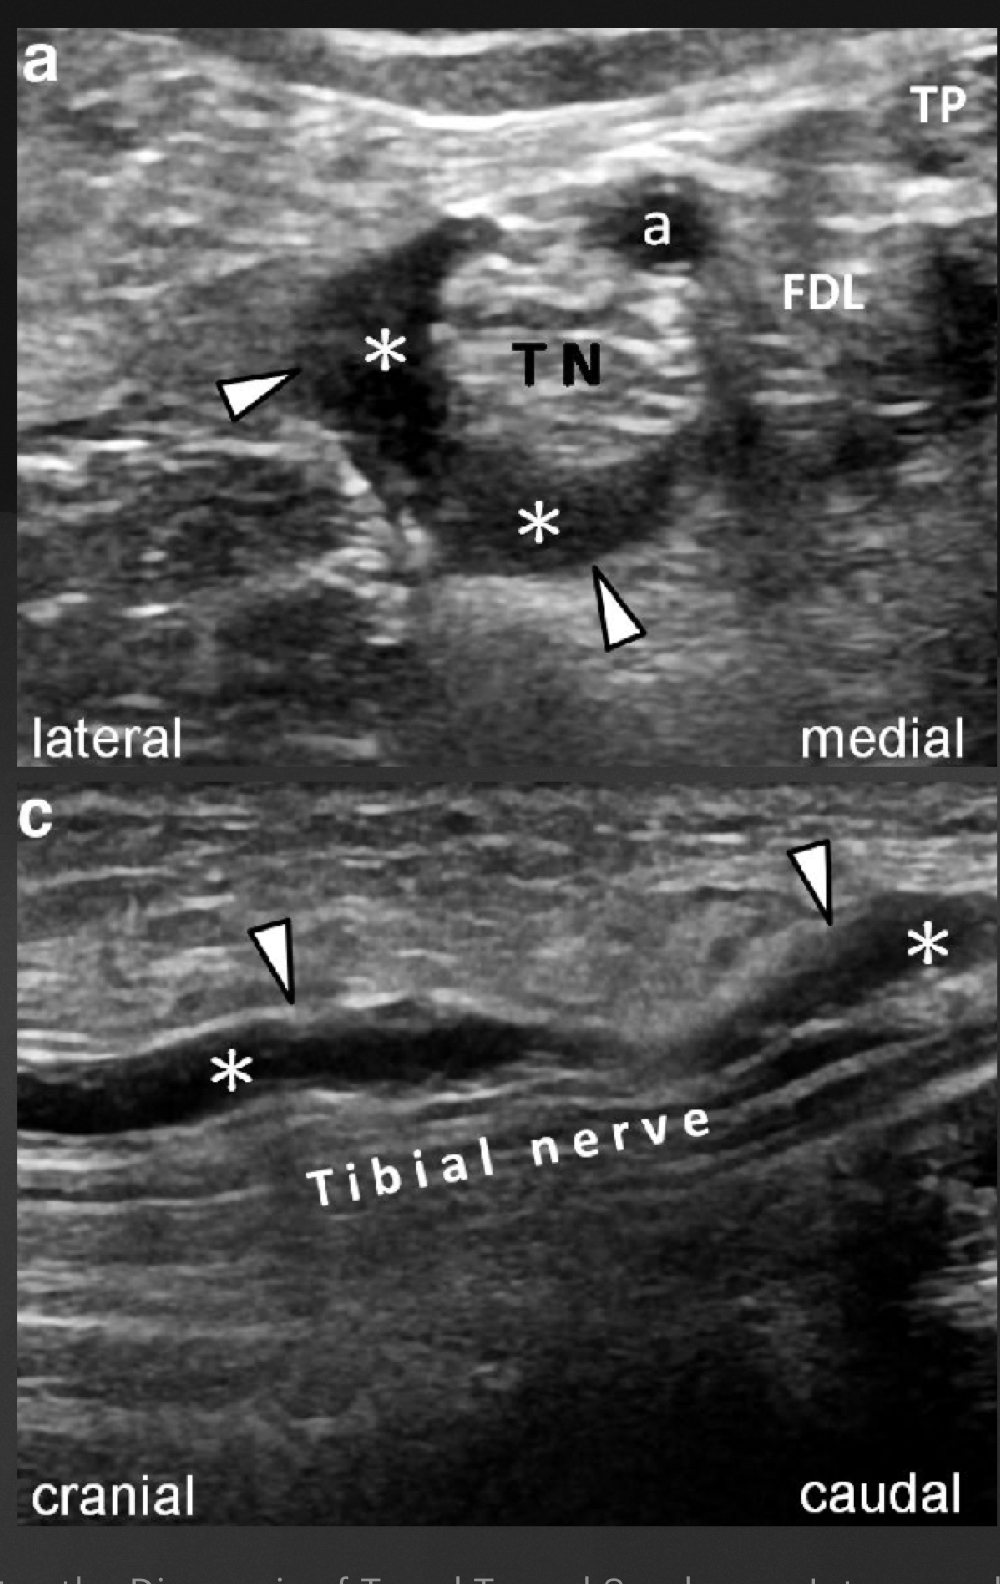

Quoi la pathologie ici?

A

Kyste ganglionnaire intra-neural (où il y a des petites étoiles

Place ta sonde sur l’image où le nerf tibial va se diviser en ses 2 branches, donc ou tu devrais le mesurer en court axe dans ton évaluation du syndrome du tunnel tarsien